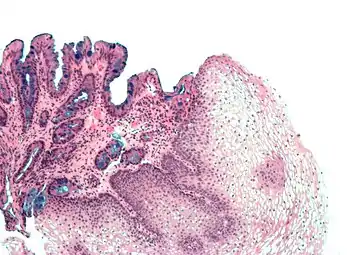

Both macroscopic (from endoscopy) and microscopic positive findings are required to make a diagnosis. Barrett's esophagus is marked by the presence of columnar epithelia in the lower esophagus, replacing the normal squamous cell epithelium—an example of metaplasia. The secretory columnar epithelium may be more able to withstand the erosive action of the gastric secretions; however, this metaplasia confers an increased risk of adenocarcinoma.[15]

Intestinal metaplasia

The presence of goblet cells, called intestinal metaplasia, is necessary to make a diagnosis of Barrett's esophagus. This frequently occurs in the presence of other metaplastic columnar cells, but only the presence of goblet cells is diagnostic. The metaplasia is grossly visible through a gastroscope, but biopsy specimens must be examined under a microscope to determine whether cells are gastric or colonic in nature. Colonic metaplasia is usually identified by finding goblet cells in the epithelium and is necessary for the true diagnosis.[20]

Many histologic mimics of Barrett's esophagus are known (i.e. goblet cells occurring in the transitional epithelium of normal esophageal submucosal gland ducts, "pseudogoblet cells" in which abundant foveolar [gastric] type mucin simulates the acid mucin true goblet cells). Assessment of relationship to submucosal glands and transitional-type epithelium with examination of multiple levels through the tissue may allow the pathologist to reliably distinguish between goblet cells of submucosal gland ducts and true Barrett's esophagus (specialized columnar metaplasia). The histochemical stain Alcian blue pH 2.5 is also frequently used to distinguish true intestinal-type mucins from their histologic mimics. Recently, immunohistochemical analysis with antibodies to CDX-2 (specific for mid and hindgut intestinal derivation) has also been used to identify true intestinal-type metaplastic cells. The protein AGR2 is elevated in Barrett's esophagus[21] and can be used as a biomarker for distinguishing Barrett epithelium from normal esophageal epithelium.[22]